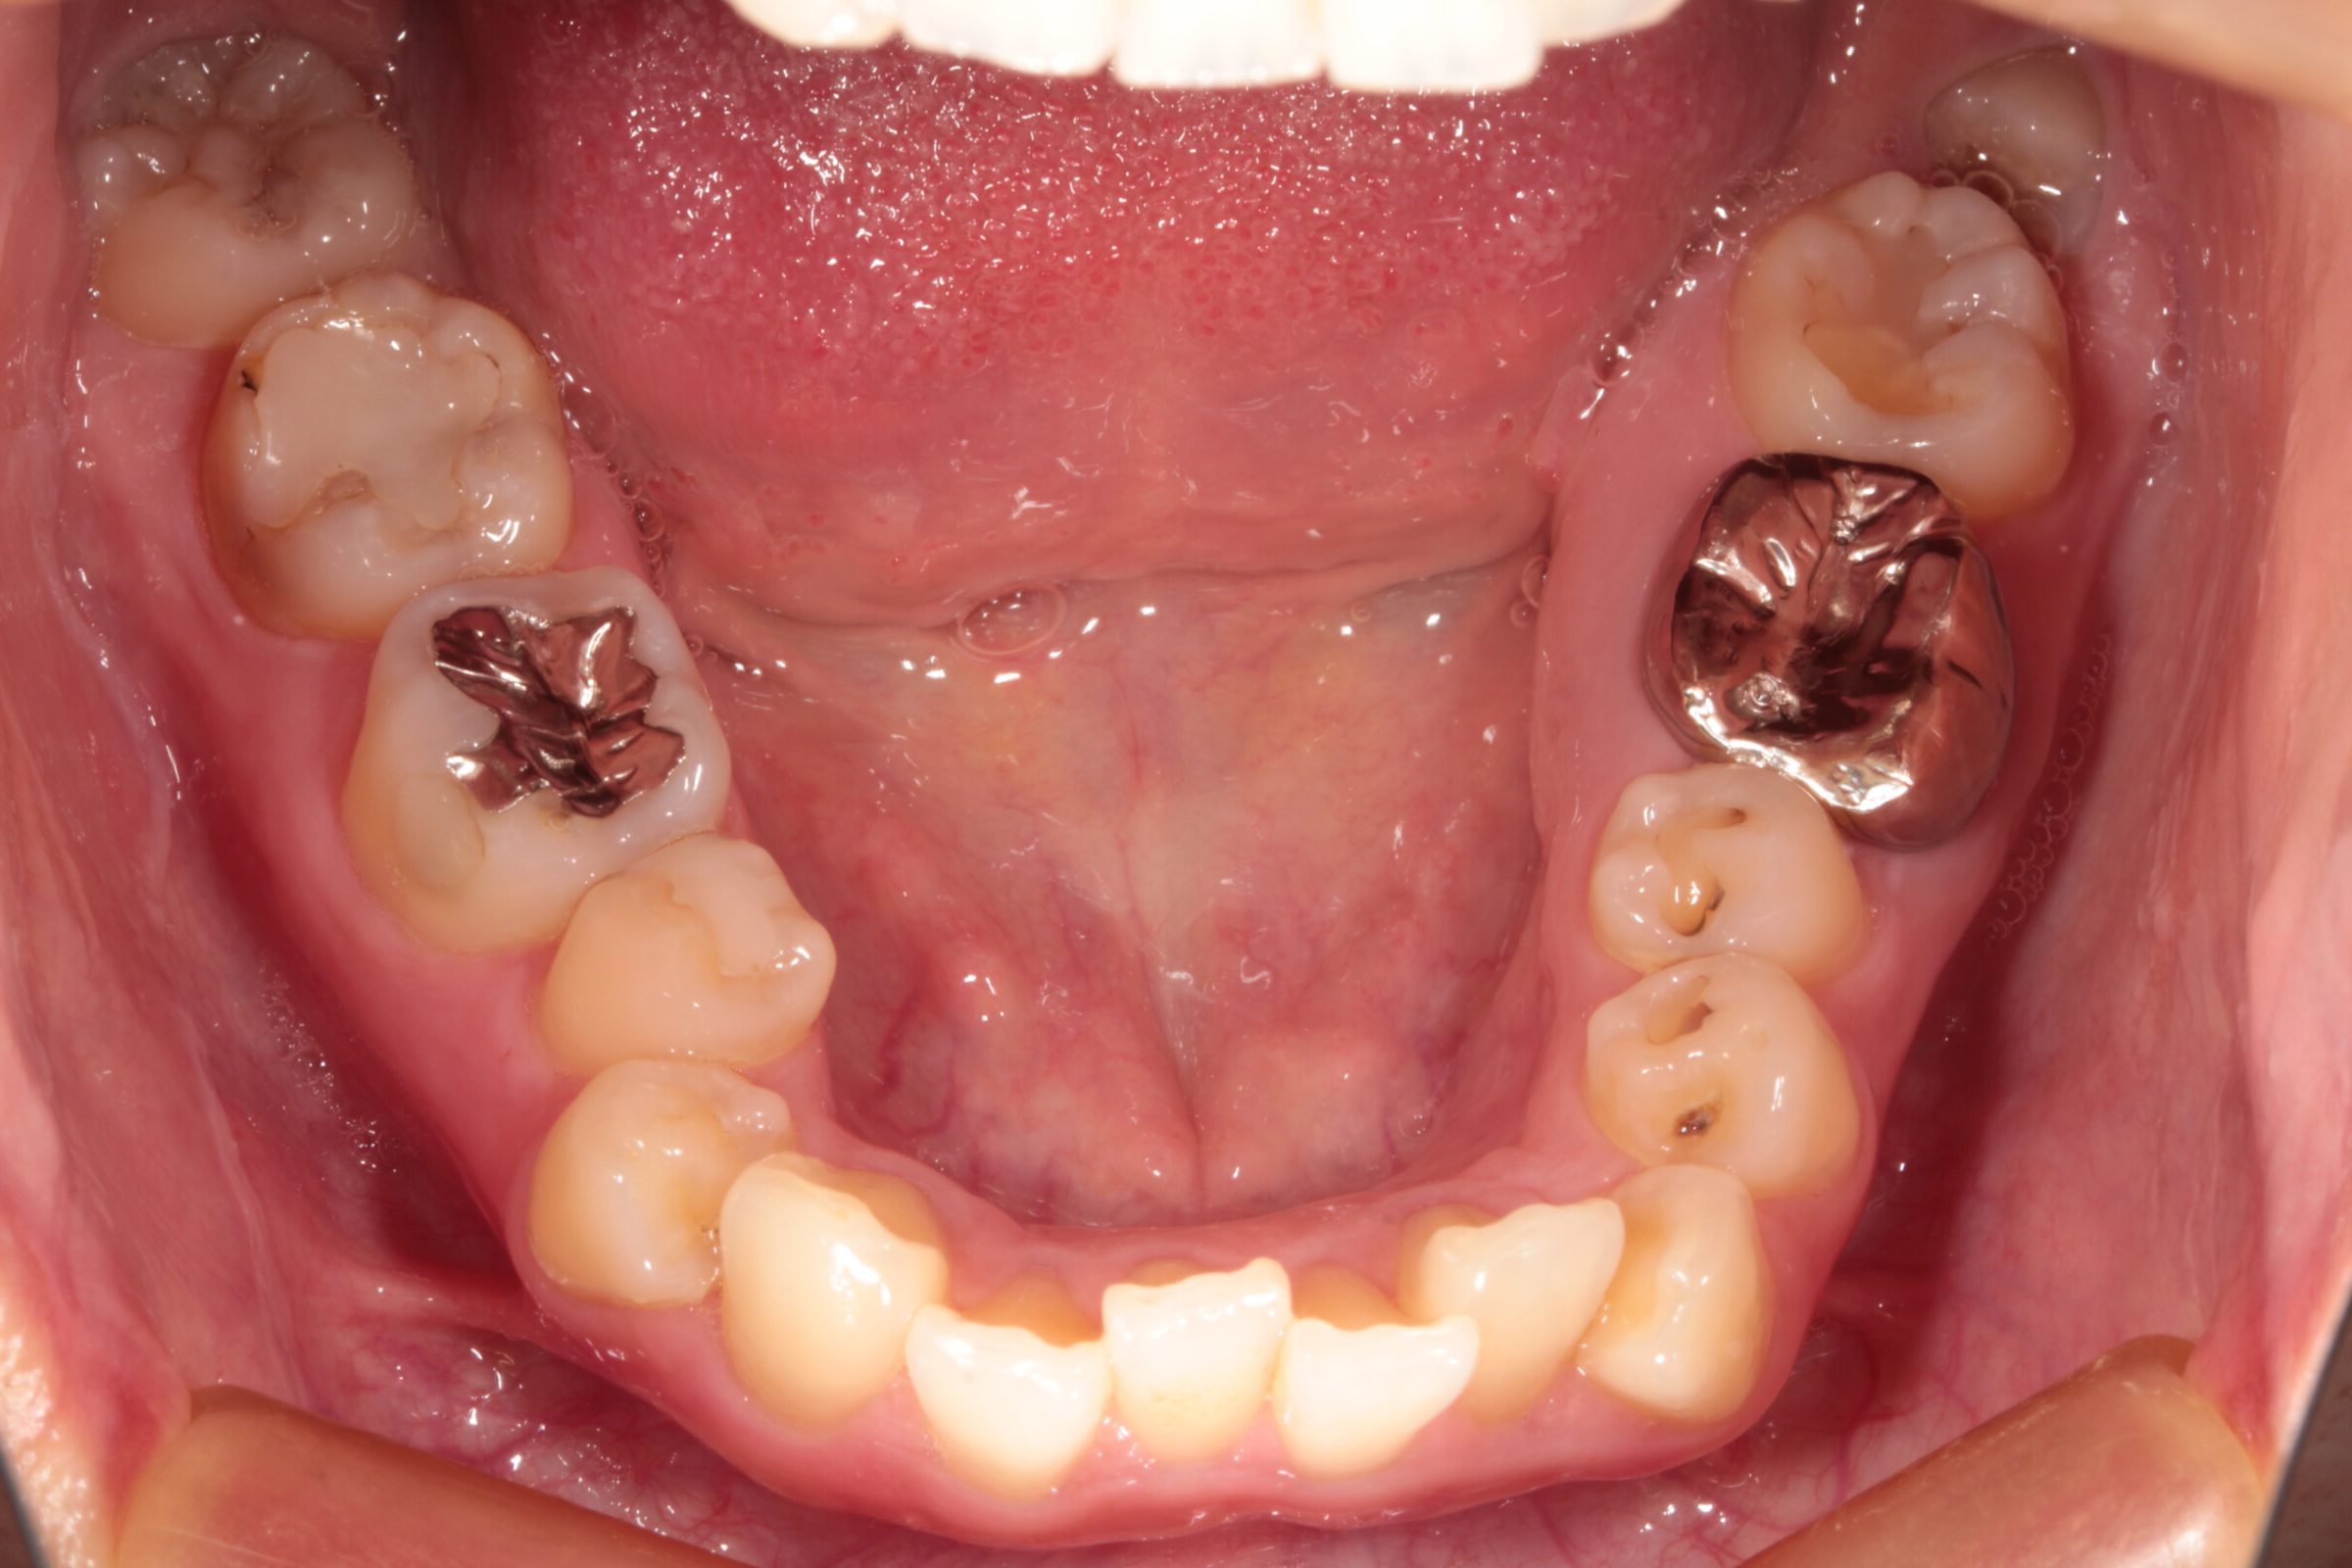

ガタガタに重なっている部分や、過去の治療で銀歯も入っています。

昔から歯は弱いほうで、トラブル続きだったこともあり、色々治療はしていましたが根本解決はせず…

当院の院長によるセラミック治療と矯正専門医の芝田Dr.によるワンストップ治療で一生困らないように治療していこうと踏み切ることが出来ました。